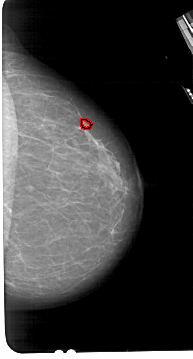

A_1871_1.LEFT_MLO

LEFT_MLO LINES 5491 PIXELS_PER_LINE 3211 BITS_PER_PIXEL 12 RESOLUTION 43.5 NON_OVERLAY

FILE: A_1871_1.RIGHT_MLO.OVERLAY

TOTAL_ABNORMALITIES 1

ABNORMALITY 1

LESION_TYPE MASS SHAPE IRREGULAR MARGINS ILL_DEFINED

ASSESSMENT 4

SUBTLETY 1

PATHOLOGY MALIGNANT

TOTAL_OUTLINES 1

BOUNDARY